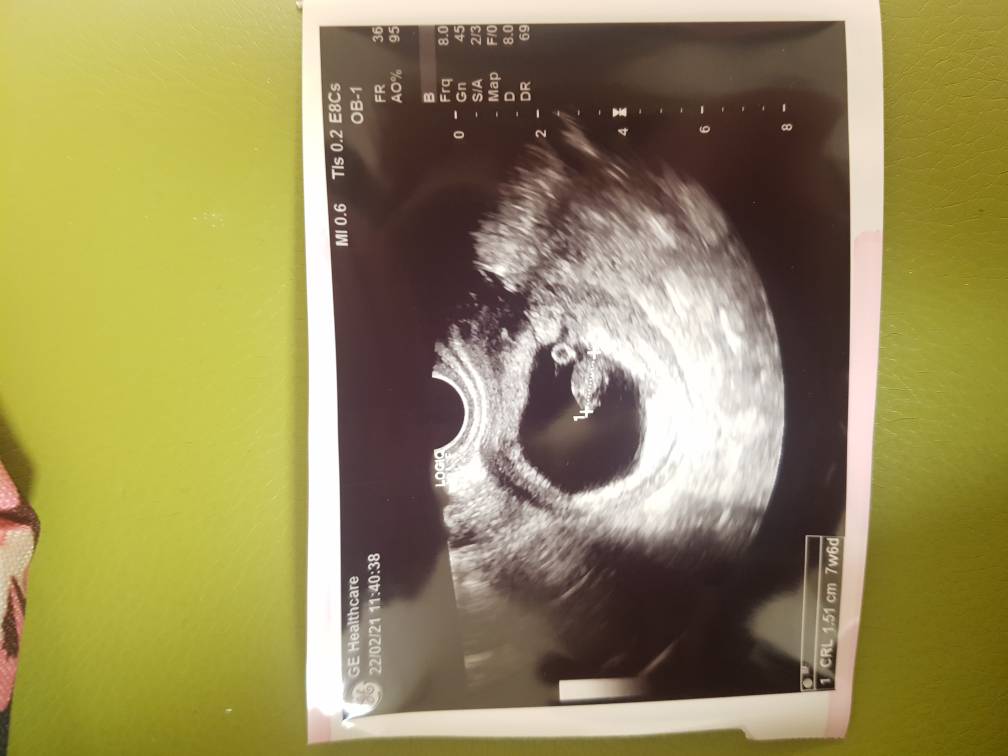

Byłam dziś w luxmedzie założyć kartę ciąży żeby robić w ramach abonamentu badania krwi od prywatnego ginekologa. Mamy 7+6. Dzidź ma 1.5 cm. Serduszko pięknie bije. Niestety pojawił się krwiak. Będę jeszcze bardziej odpoczywać. Macie jakieś doświadczenia? Mogę coś jeszcze zrobić?

Piękne zdjęcie 😍 najważniejsze, ze wszystko w porządku. Ja jak byłam w zeszłym tyg i mówił ze ma podejrzenia krwiaka bądź drugiego lokatora, przepisał mi dupka 2X1 a Tobie coś przepisał lekarz? Kazał mi dużo odpoczywać. Czytałam na forach to jest to dość częste, w większości się wchłaniają w zależności od wielkości albo poprostu występują plamienia takie brązowe bo się oczyszcza. A mówił coś jakiej wielkości ? No i chyba ważne czy blisko dzidzi jest 🤔 może ktoś bardziej doświadczony się wypowie dziewczyny??? ☺️☺️